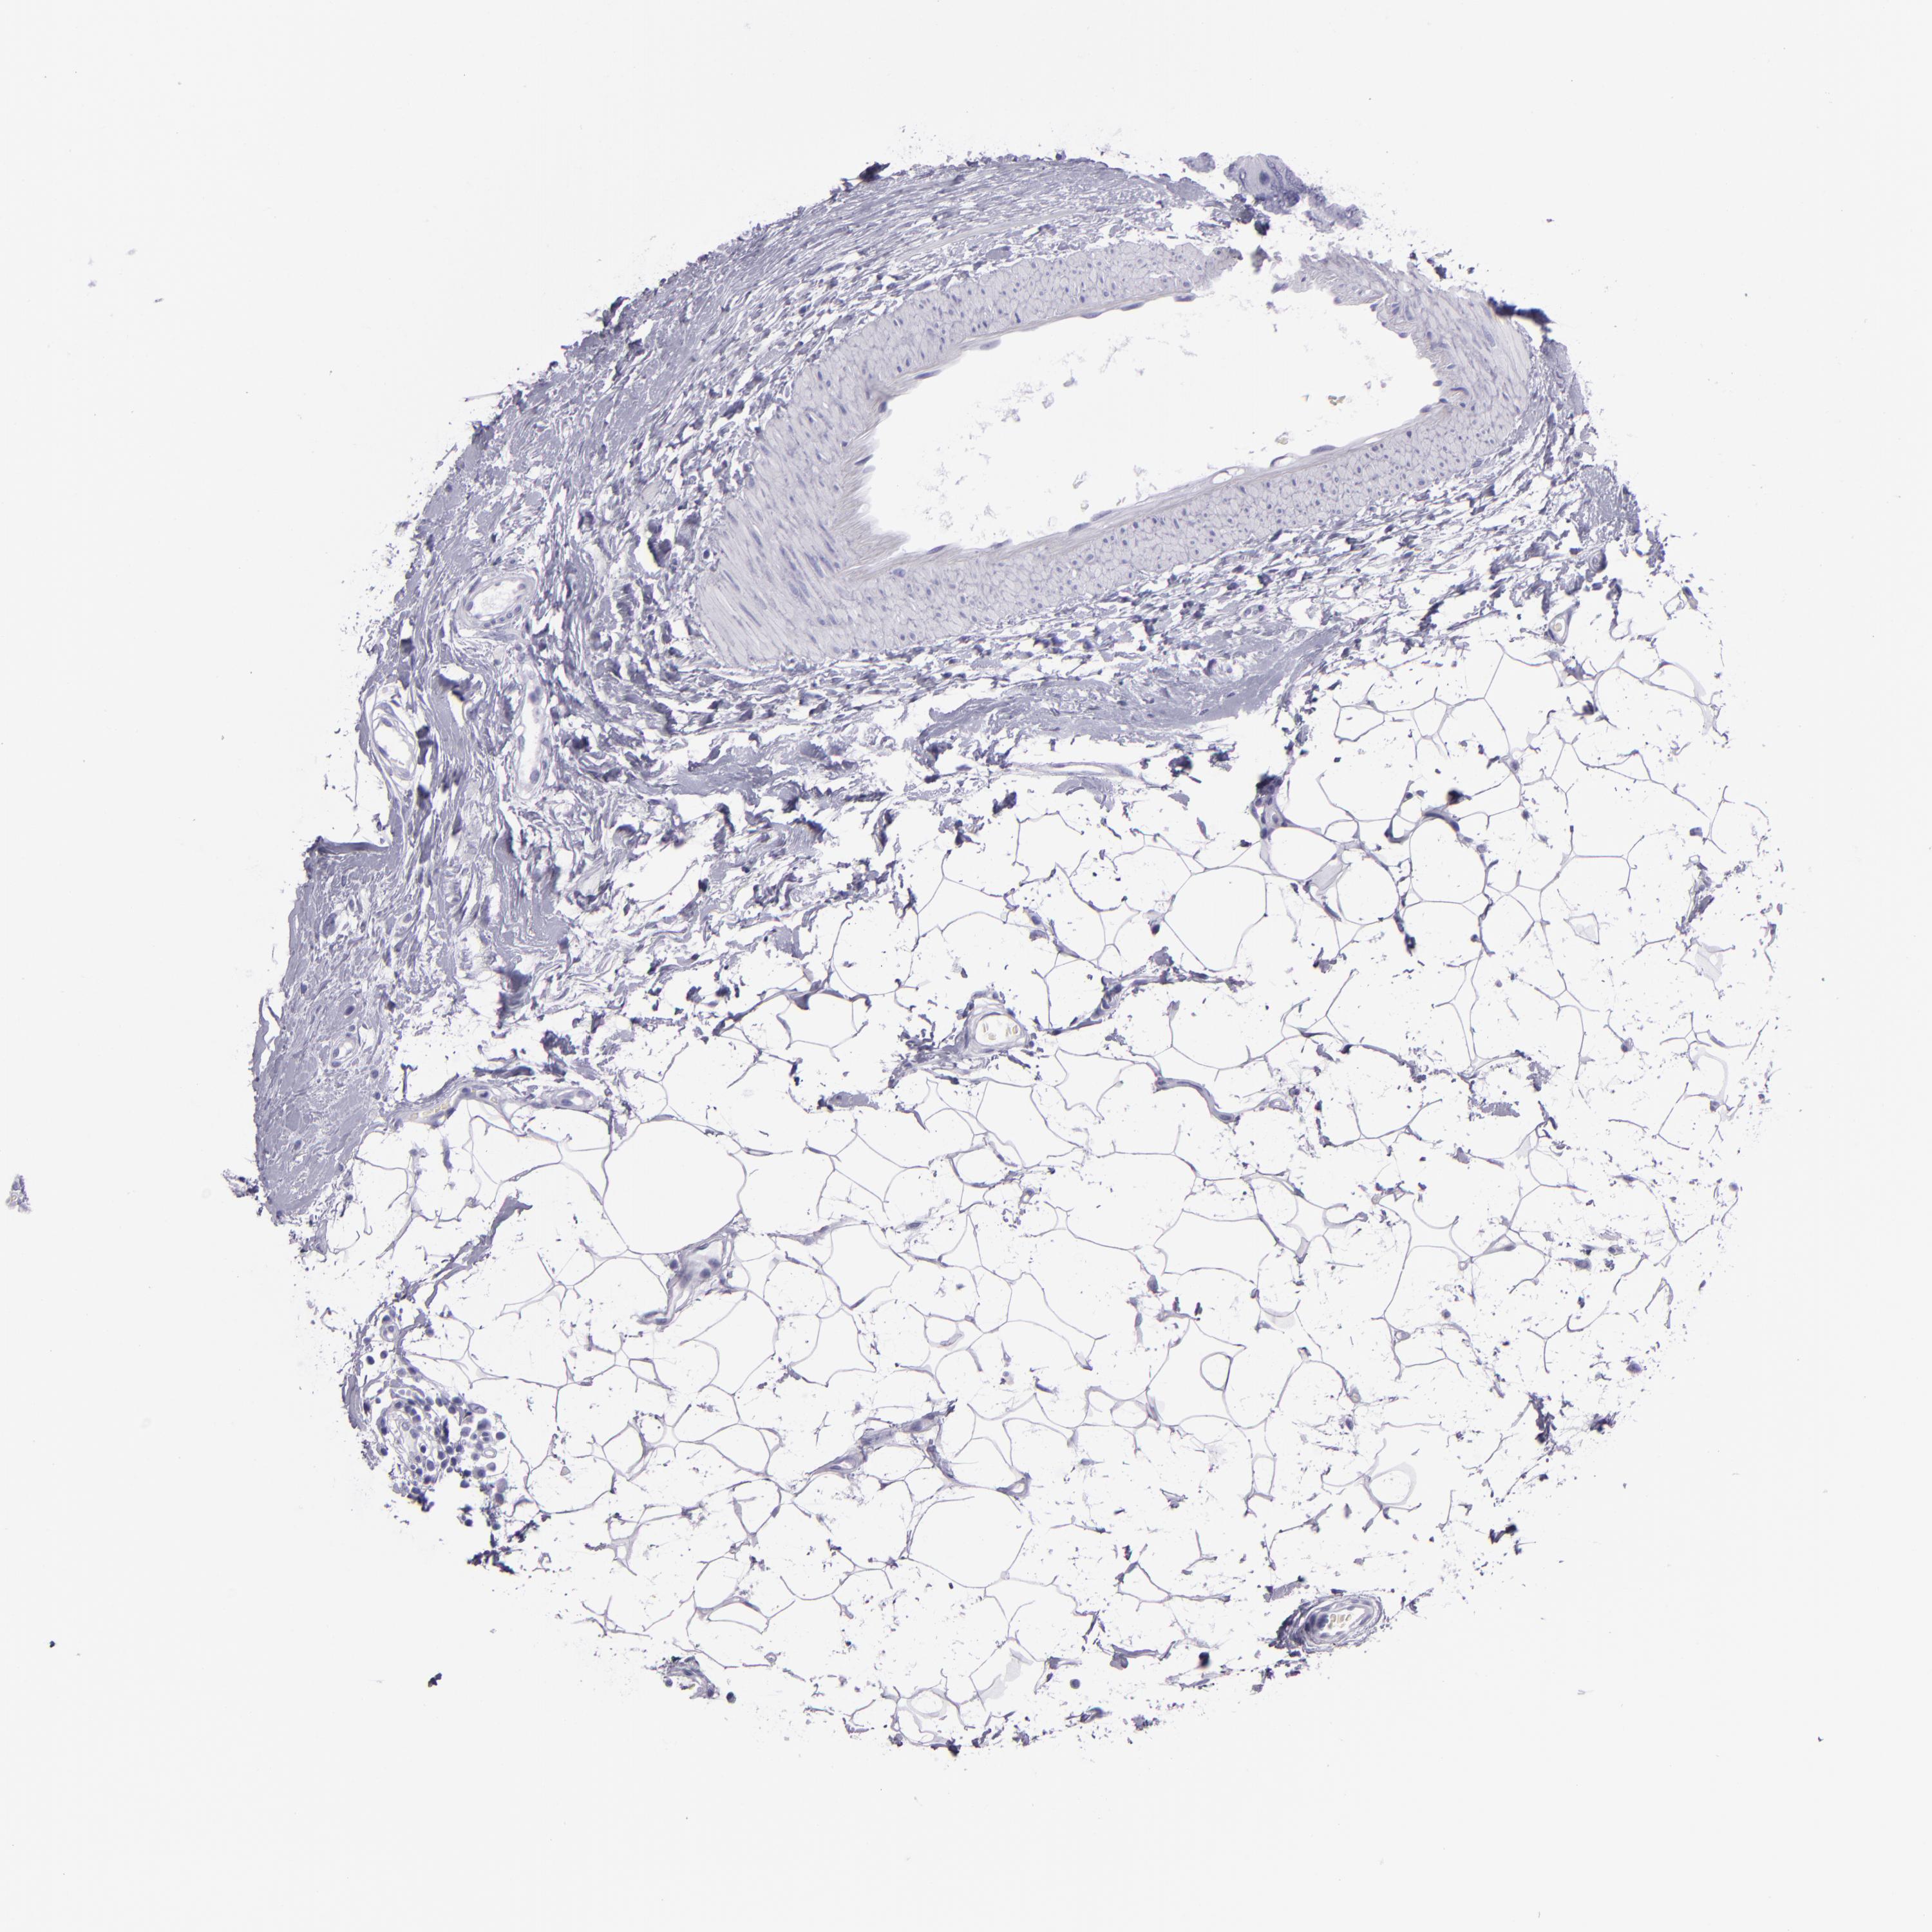

BRCA TCGA BRCA VALIDATION PROTEIN EXPRESSION

Breast cancer

Human cancer